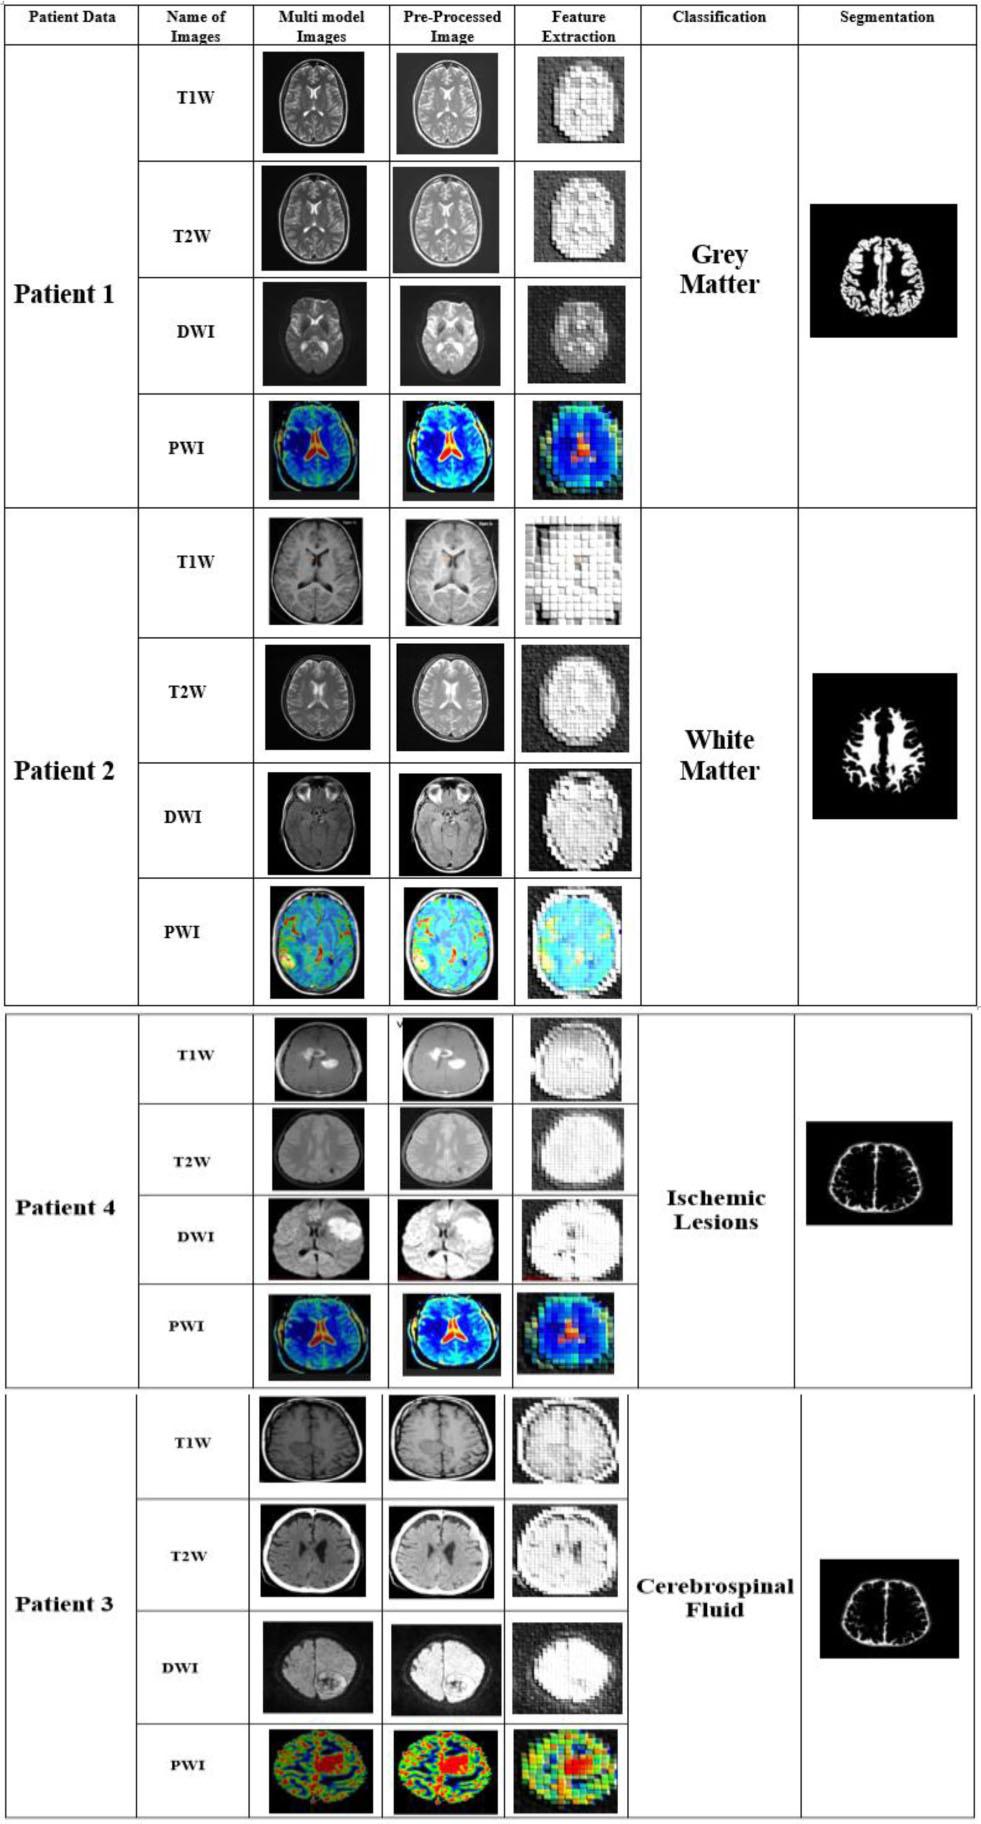

Fig. 6 illustrates the virtual result of the proposed BTS-NEUNET method using the ADNI and ISLES datasets. The patient data are described in column 1. The names of the multimodal MRI images, such as T1W, T2W, DWI, and PWI, are displayed in column 2. The brain's multimodal MRI images are presented in column 3. The pre-processed multimodal images are described in column 4. The feature extracted images are illustrated in column 5. Column 6 shows the four classification outcomes of the proposed BTS-NEUNET approach. Finally, the segmented output of the brain tissue is illustrated in column 7.

Experimental result of the proposed BTS-NEUNET.